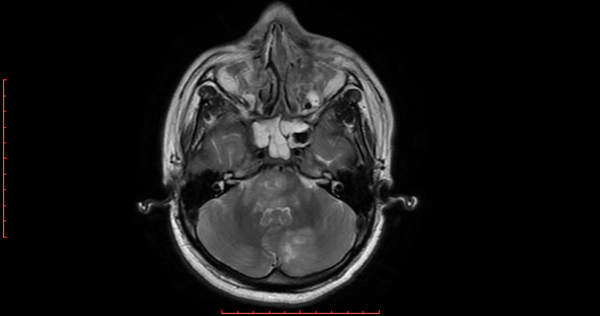

h. 2) Resonancia magnética cerebral de corte axial en secuencia T1 con gadolinio. Se identificó a nivel del puente y pedúnculos cerebolosos una imagen con efecto de masa y reforzamiento en el interior; en el hemisferio izquierdo se observó una imagen heterogénea, con zonas de reforzamiento al medio de contraste en el interior. (Figura 2).

Figura 2. Resonancia magnética cerebral corte axial en secuencia T1 con gadolinio.